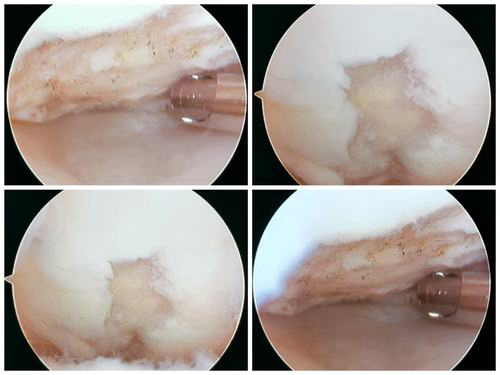

1展示关节镜微创技术:凝胶修复软骨损伤(髌骨软骨损伤凝胶支架修复)

2 膝关节股骨滑车软骨损伤凝胶支架修复

滑车软骨损伤 (软骨剥脱,软骨下骨暴露)

清理微骨折处理

微骨折后骨髓骨细胞溢出

注射凝胶支架覆盖软骨损伤区

软骨修复后(完全覆盖填充)